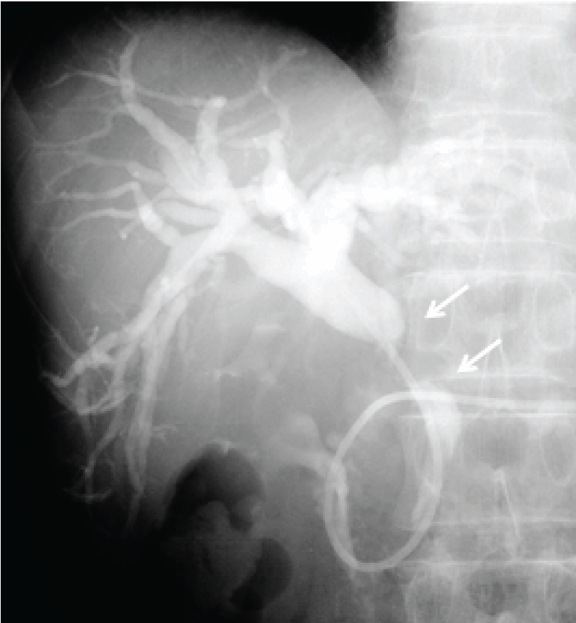

A 67-year-old male patient was referred to our hospital to investigate a case of jaundice on October 2010. He denied anorexia, abdominal pain, alcohol abuse and cigarette smoking. Physical examination revealed a mildly cachectic and icteric male with no acute distress. An abdominal examination revealed no palpable abdominal masses, organomegaly or evidence of ascites. He denied abdominal tenderness. On admission his total bilirubin level 7.52 mg/dL, alkaline phosphatase 1032 IU/L (normal range 105–320 IU/L), carcinoembryonic antigen 11.8 ng/dL (range, 0.0–5.0 ng/dL), carbohydrate antigen 19–9 was 765.1 Um/L (normal range 0.0-37.0 U/mL). Ultrasonography and contrast-enhanced computed tomography (CT) of the abdomen revealed a mass, approximately 2 cm in diameter, in the middle of the common bile duct (CBD), which caused the dilatation of the proximal biliary tract. (Figure 1A–B) Endoscopic retrograde naso-biliary drainage was successfully performed to improve the jaundice. Cholangiography and magnetic resonance cholangiopancreatography revealed a 2.5-cm filling defect in the middle of the CBD. (Figure 2) Based on these findings, the patient was diagnosed with middle bile duct cancer and a subtotal-stomach-preserving PD was planned.

Figure 1: (A) Abdominal ultrasonography showing a low echoic mass (arrows) in the middle of the common bile duct, which caused the dilatation of the proximal biliary tract, (B) Contrast-enhanced computed tomography of the abdomen showing a tumor (arrows) in the middle of the common bile duct, approximately 2 cm in diameter, which resulted in dilatation of the proximal biliary tract.